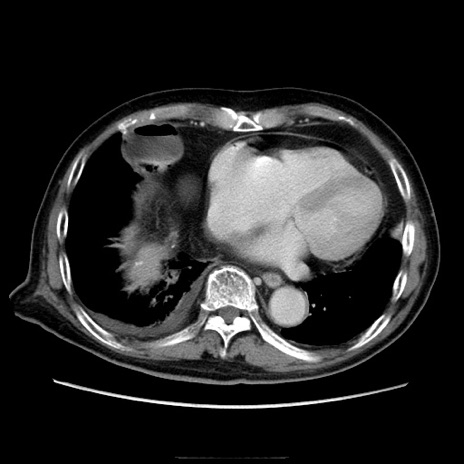

冠状断像

症例21(横断像)

【症例】70歳代男性

【主訴】腹痛

【現病歴】肝硬変・肝細胞癌にてかかりつけの方。約9時間前に食後より腹痛出現。症状が徐々に増悪し、嘔吐出現したため来院。

【既往歴】肝硬変、肝細胞癌(RFA、TACE後)

【身体所見】意識清明、表情苦悶様、BT 36℃、BP 129/78mmHg、P 88bpm、SpO2 97%(RA)、右上腹部から心窩部にかけて圧痛あり、反跳痛なし、筋性防御あり。

【データ】WBC 5800、CRP 0.16